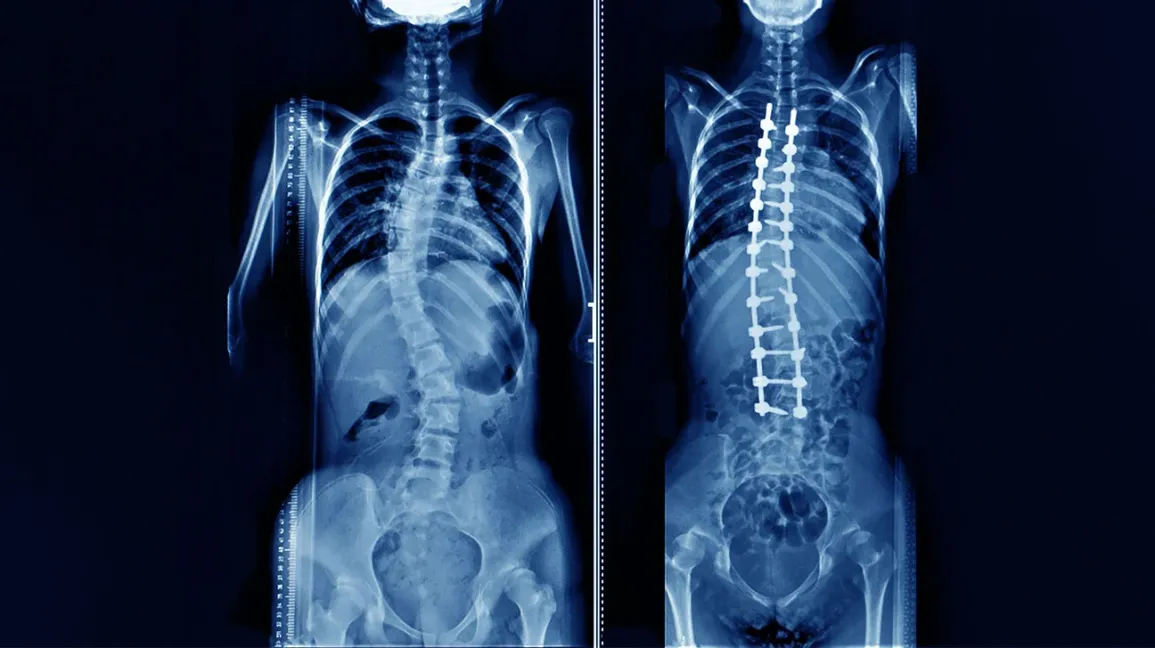

At Vidarbha Institute of Spine Surgery, we specialize in comprehensive diagnosis and advanced surgical correction for scoliosis—a condition that causes abnormal curvature of the spine. Our goal is to help patients regain proper spinal alignment, improve posture, relieve pain, and restore confidence in movement through world-class surgical expertise and personalized care.

Scoliosis is a condition where the spine curves sideways, forming an “S” or “C” shape instead of remaining straight. It can occur at any age but is most commonly detected during adolescence. While mild curves may not cause major problems, severe curvatures can lead to pain, breathing difficulty, and visible deformity.

This is the most common surgical procedure for scoliosis correction. The surgeon straightens the spine as much as safely possible and then fuses the affected vertebrae using bone grafts, rods, and screws.